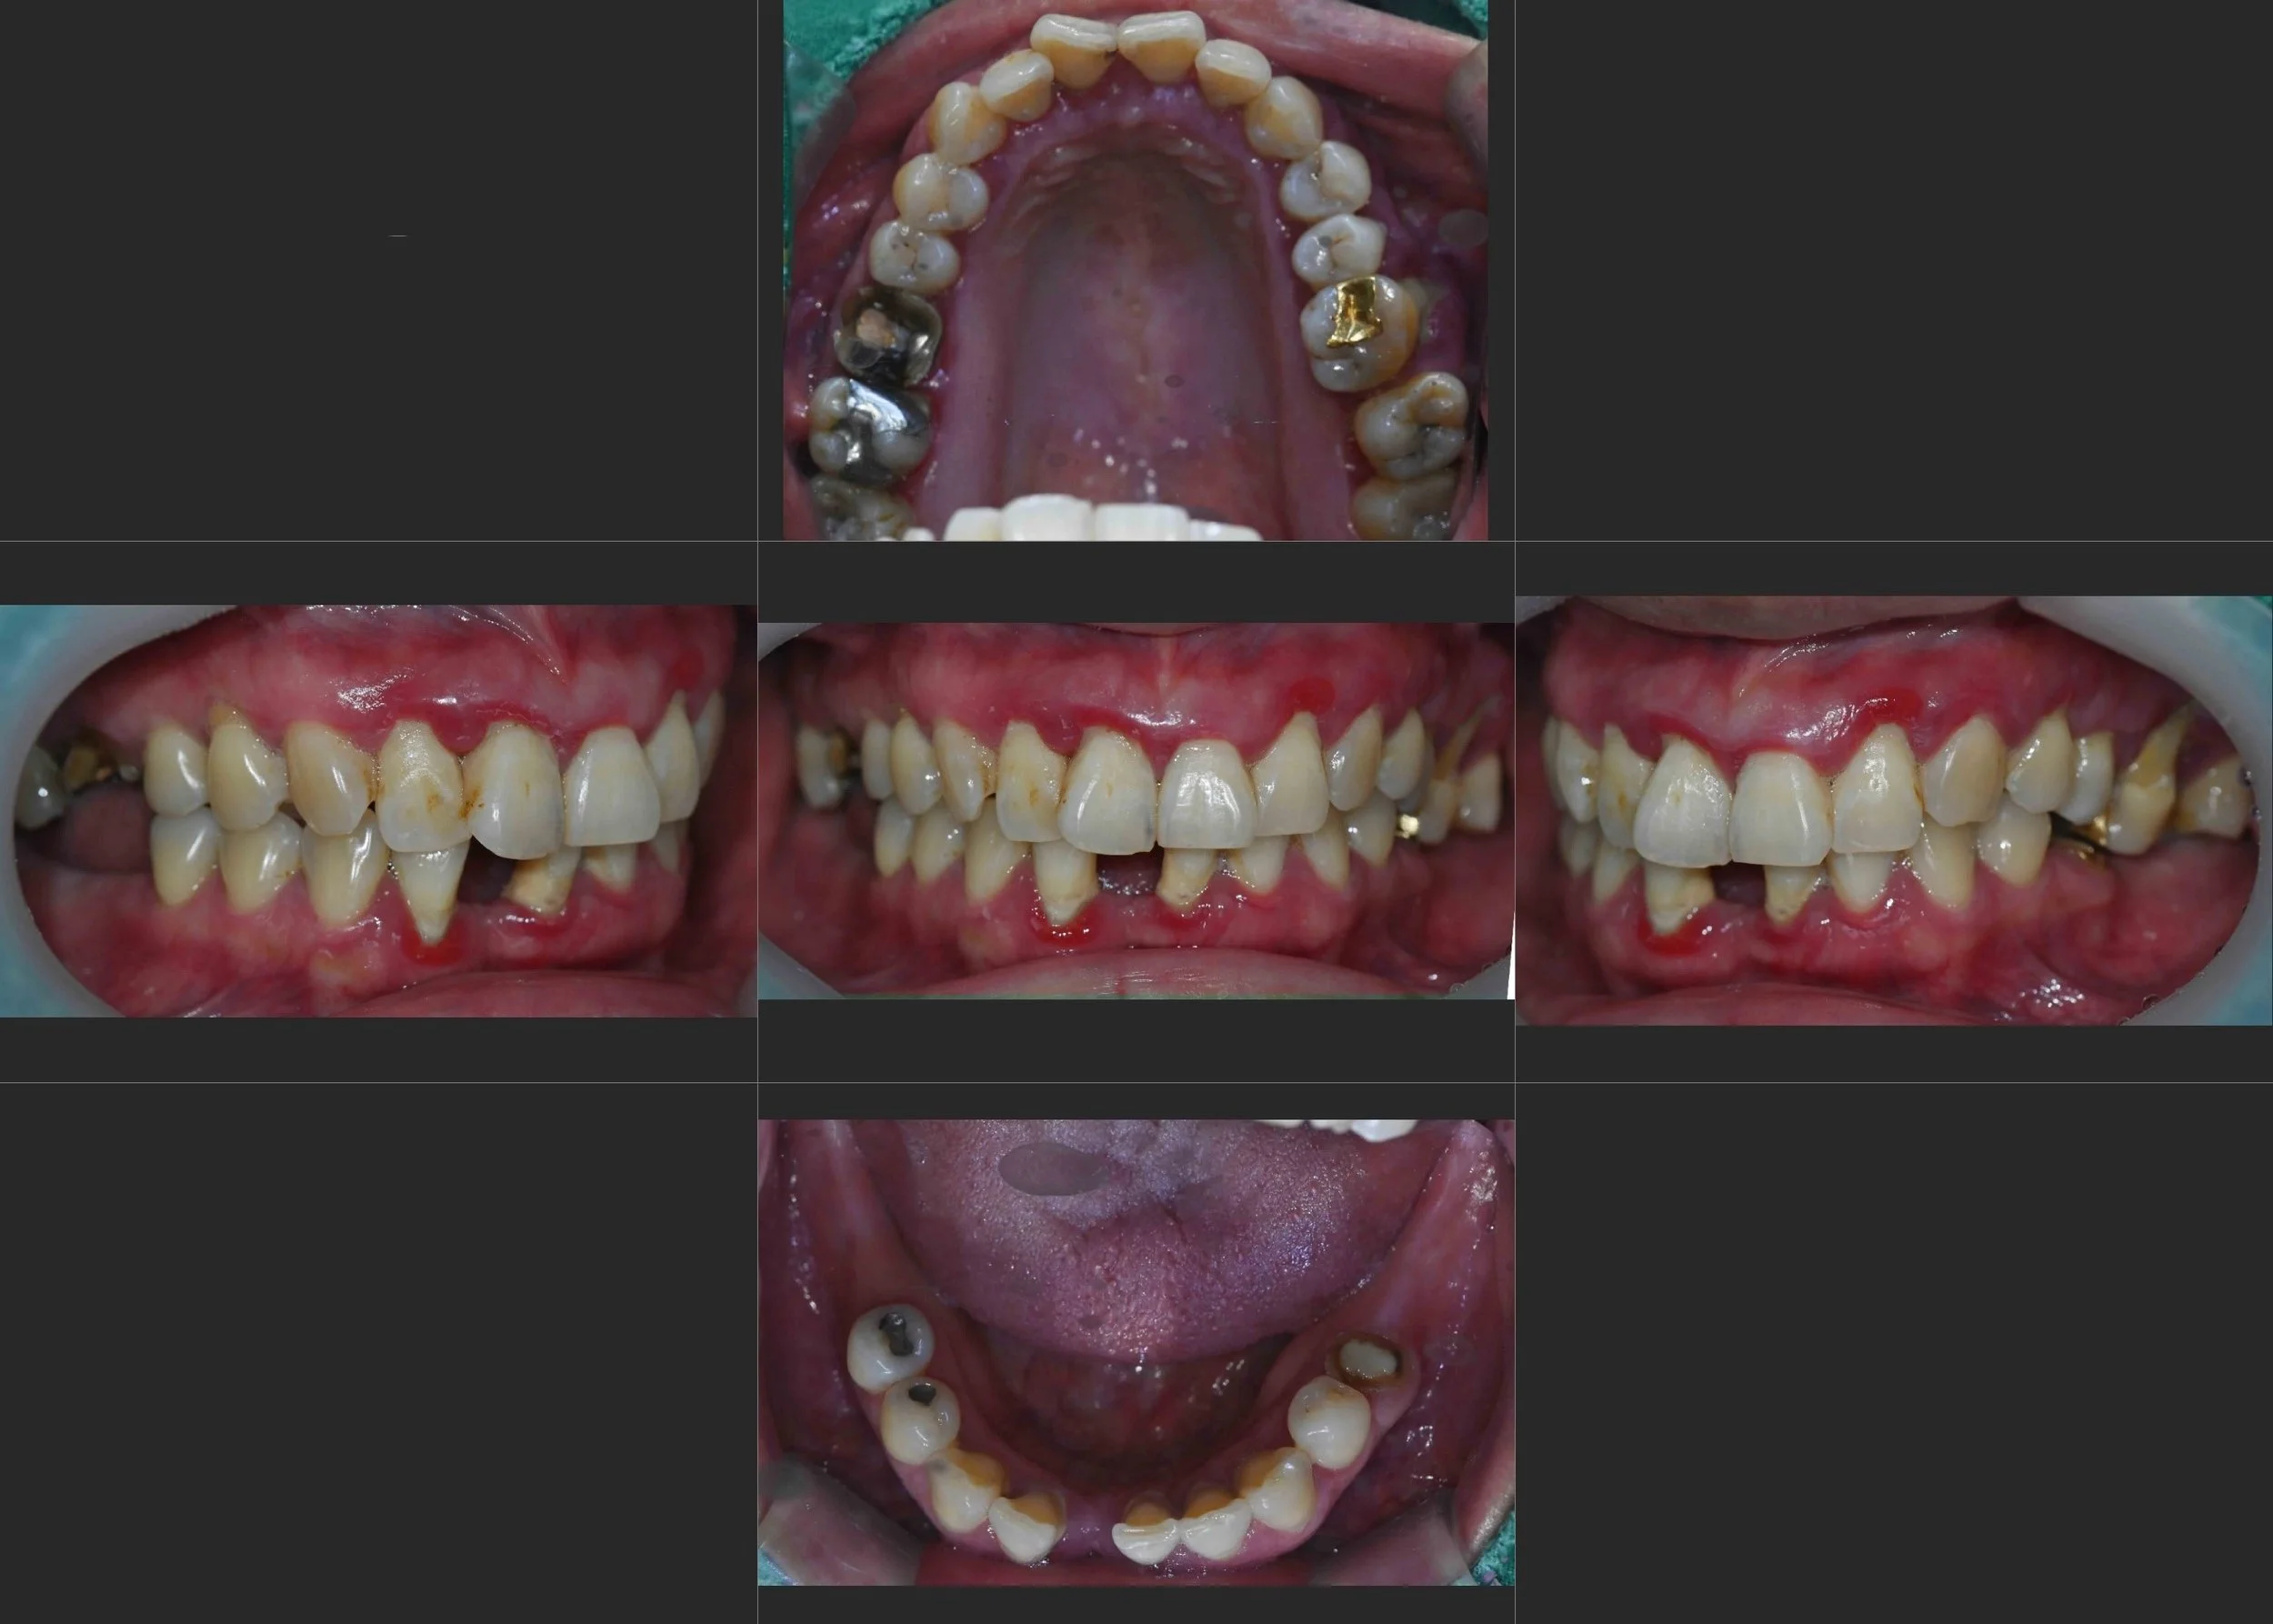

39. Comprehensive Full-Arch Rehabilitation: Overcoming Severe Bone Atrophy and Occlusal Collapse

Management of Generalized Alveolar Resorption and Failing Existing Prosthetics in a Female Patient in her 60s. A Systematic Approach via Bilateral Sinus Augmentation and VDO Elevation.

38. Comprehensive Full-Arch Reconstruction: Reversing the Domino Effect of Tooth Loss

Management of Generalized Severe Periodontitis and Posterior Bite Collapse in a Female Patient in her 60s. A Systematic Approach to VDO Recovery and Strategic Esthetic Rejuvenation.